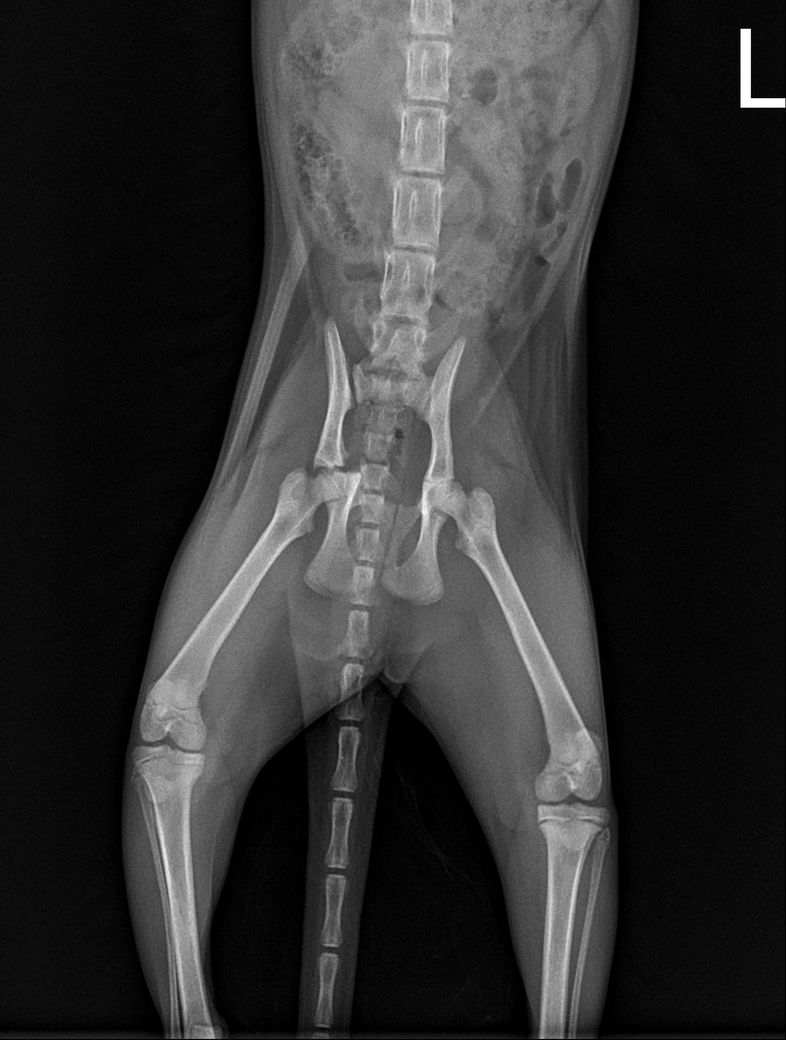

고양이 고관절 골절 진단받았는데 병원에서는 수복수술 해야한다고 하는데 자연적으로 붙는곳이아닌가요 ? 그리고 예후가 괜찮을까요 ? 수술한다고해서? 예후가 안괜찮다하면 어떤식으로 안좋을까요 ?

예, 사진상 우측 고관절의 관절면이 포함된 골절이기에 하중이 가해지는 장소인 바 자연 치유는 후천적 기형을 유도하게 되고, 수술을 하더라도 관절면이 포함된 상태로 예후는 불량한 수준입니다. 때문에 단순한 유합수술이 아닌 대퇴골두골목절단술을 동반해야 합니다.